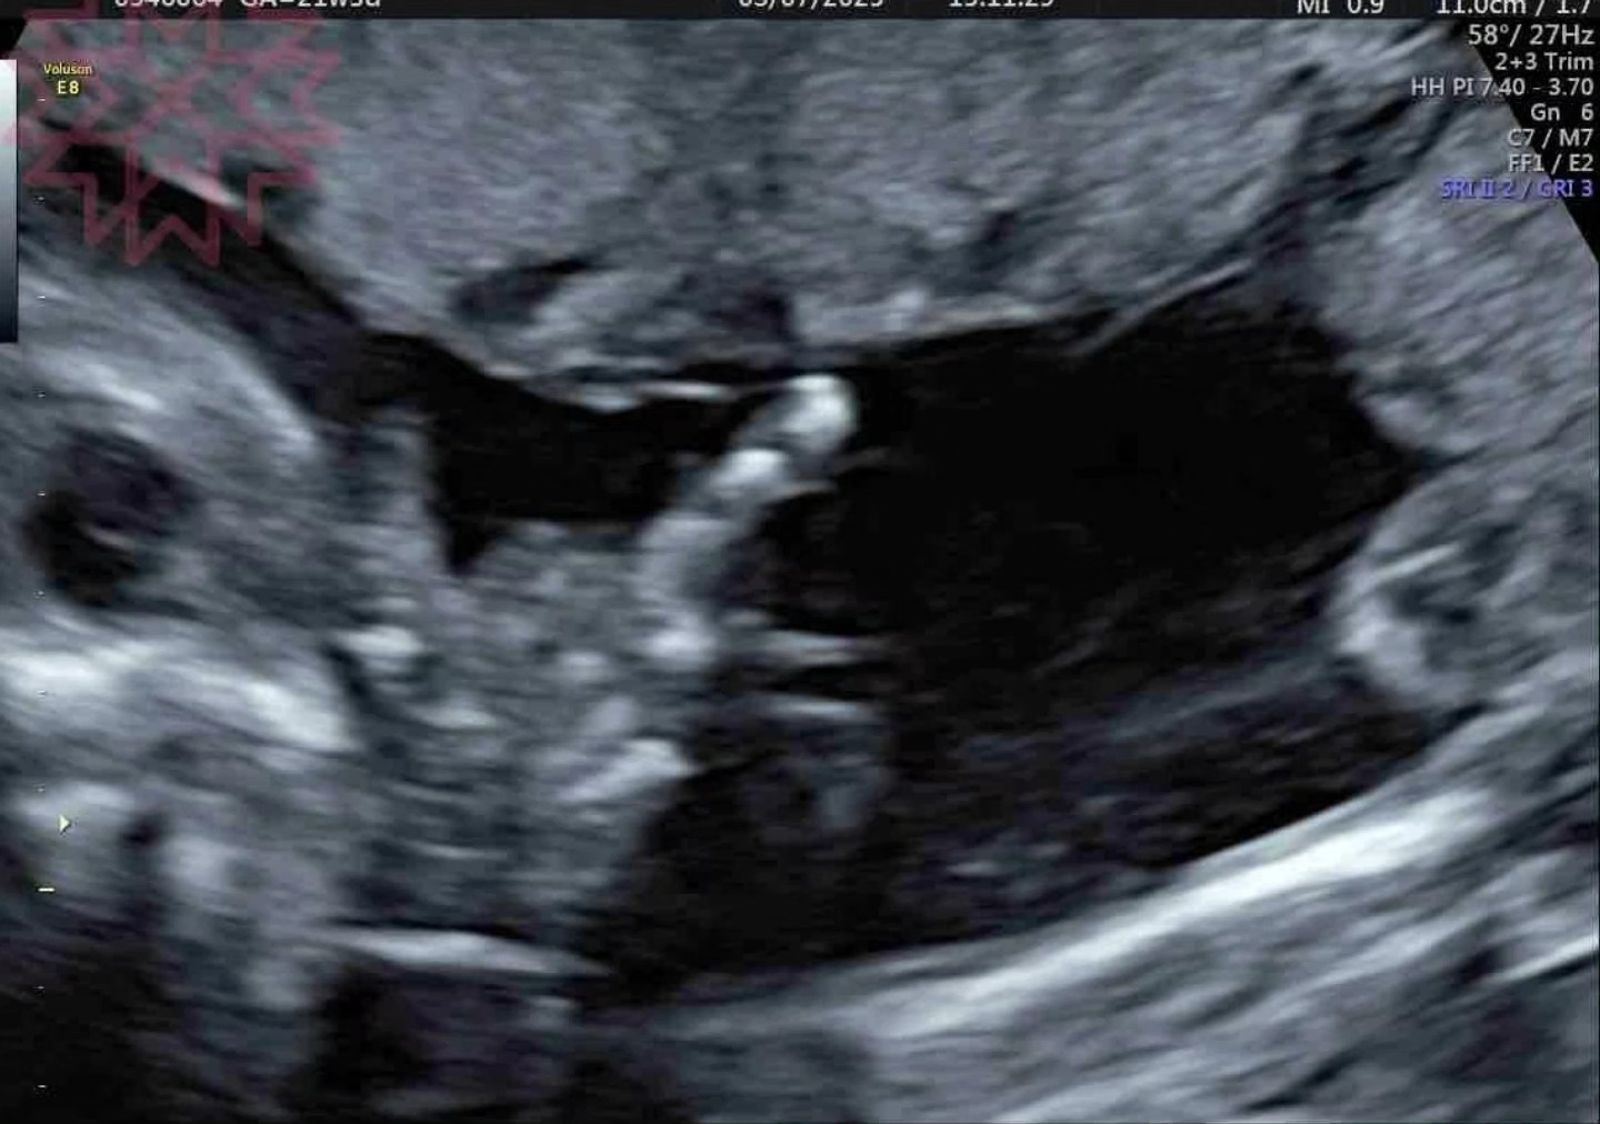

威廉表示,老婆胎中女娃目前已經6個多月大,預產期則在今年7月,兒子「百香果」對老婆懷女娃還沒有太大反應,「但是已經會幫媽媽擦肚子油,跟他說有妹妹在肚子裡,所以他一直覺得妹妹跟肚肚是一樣的,檸檬非常的酷,做高層次超音波直接比出“國際不雅手勢”,看來我不用太擔心她未來會不會被欺負,哈哈很期待百香檸檬的組合會蹦出什麼樣的新滋味呢」。